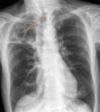

Q

A

Consolidación alveolar

How well did you know this?

1

Not at all

2

3

4

5

Perfectly